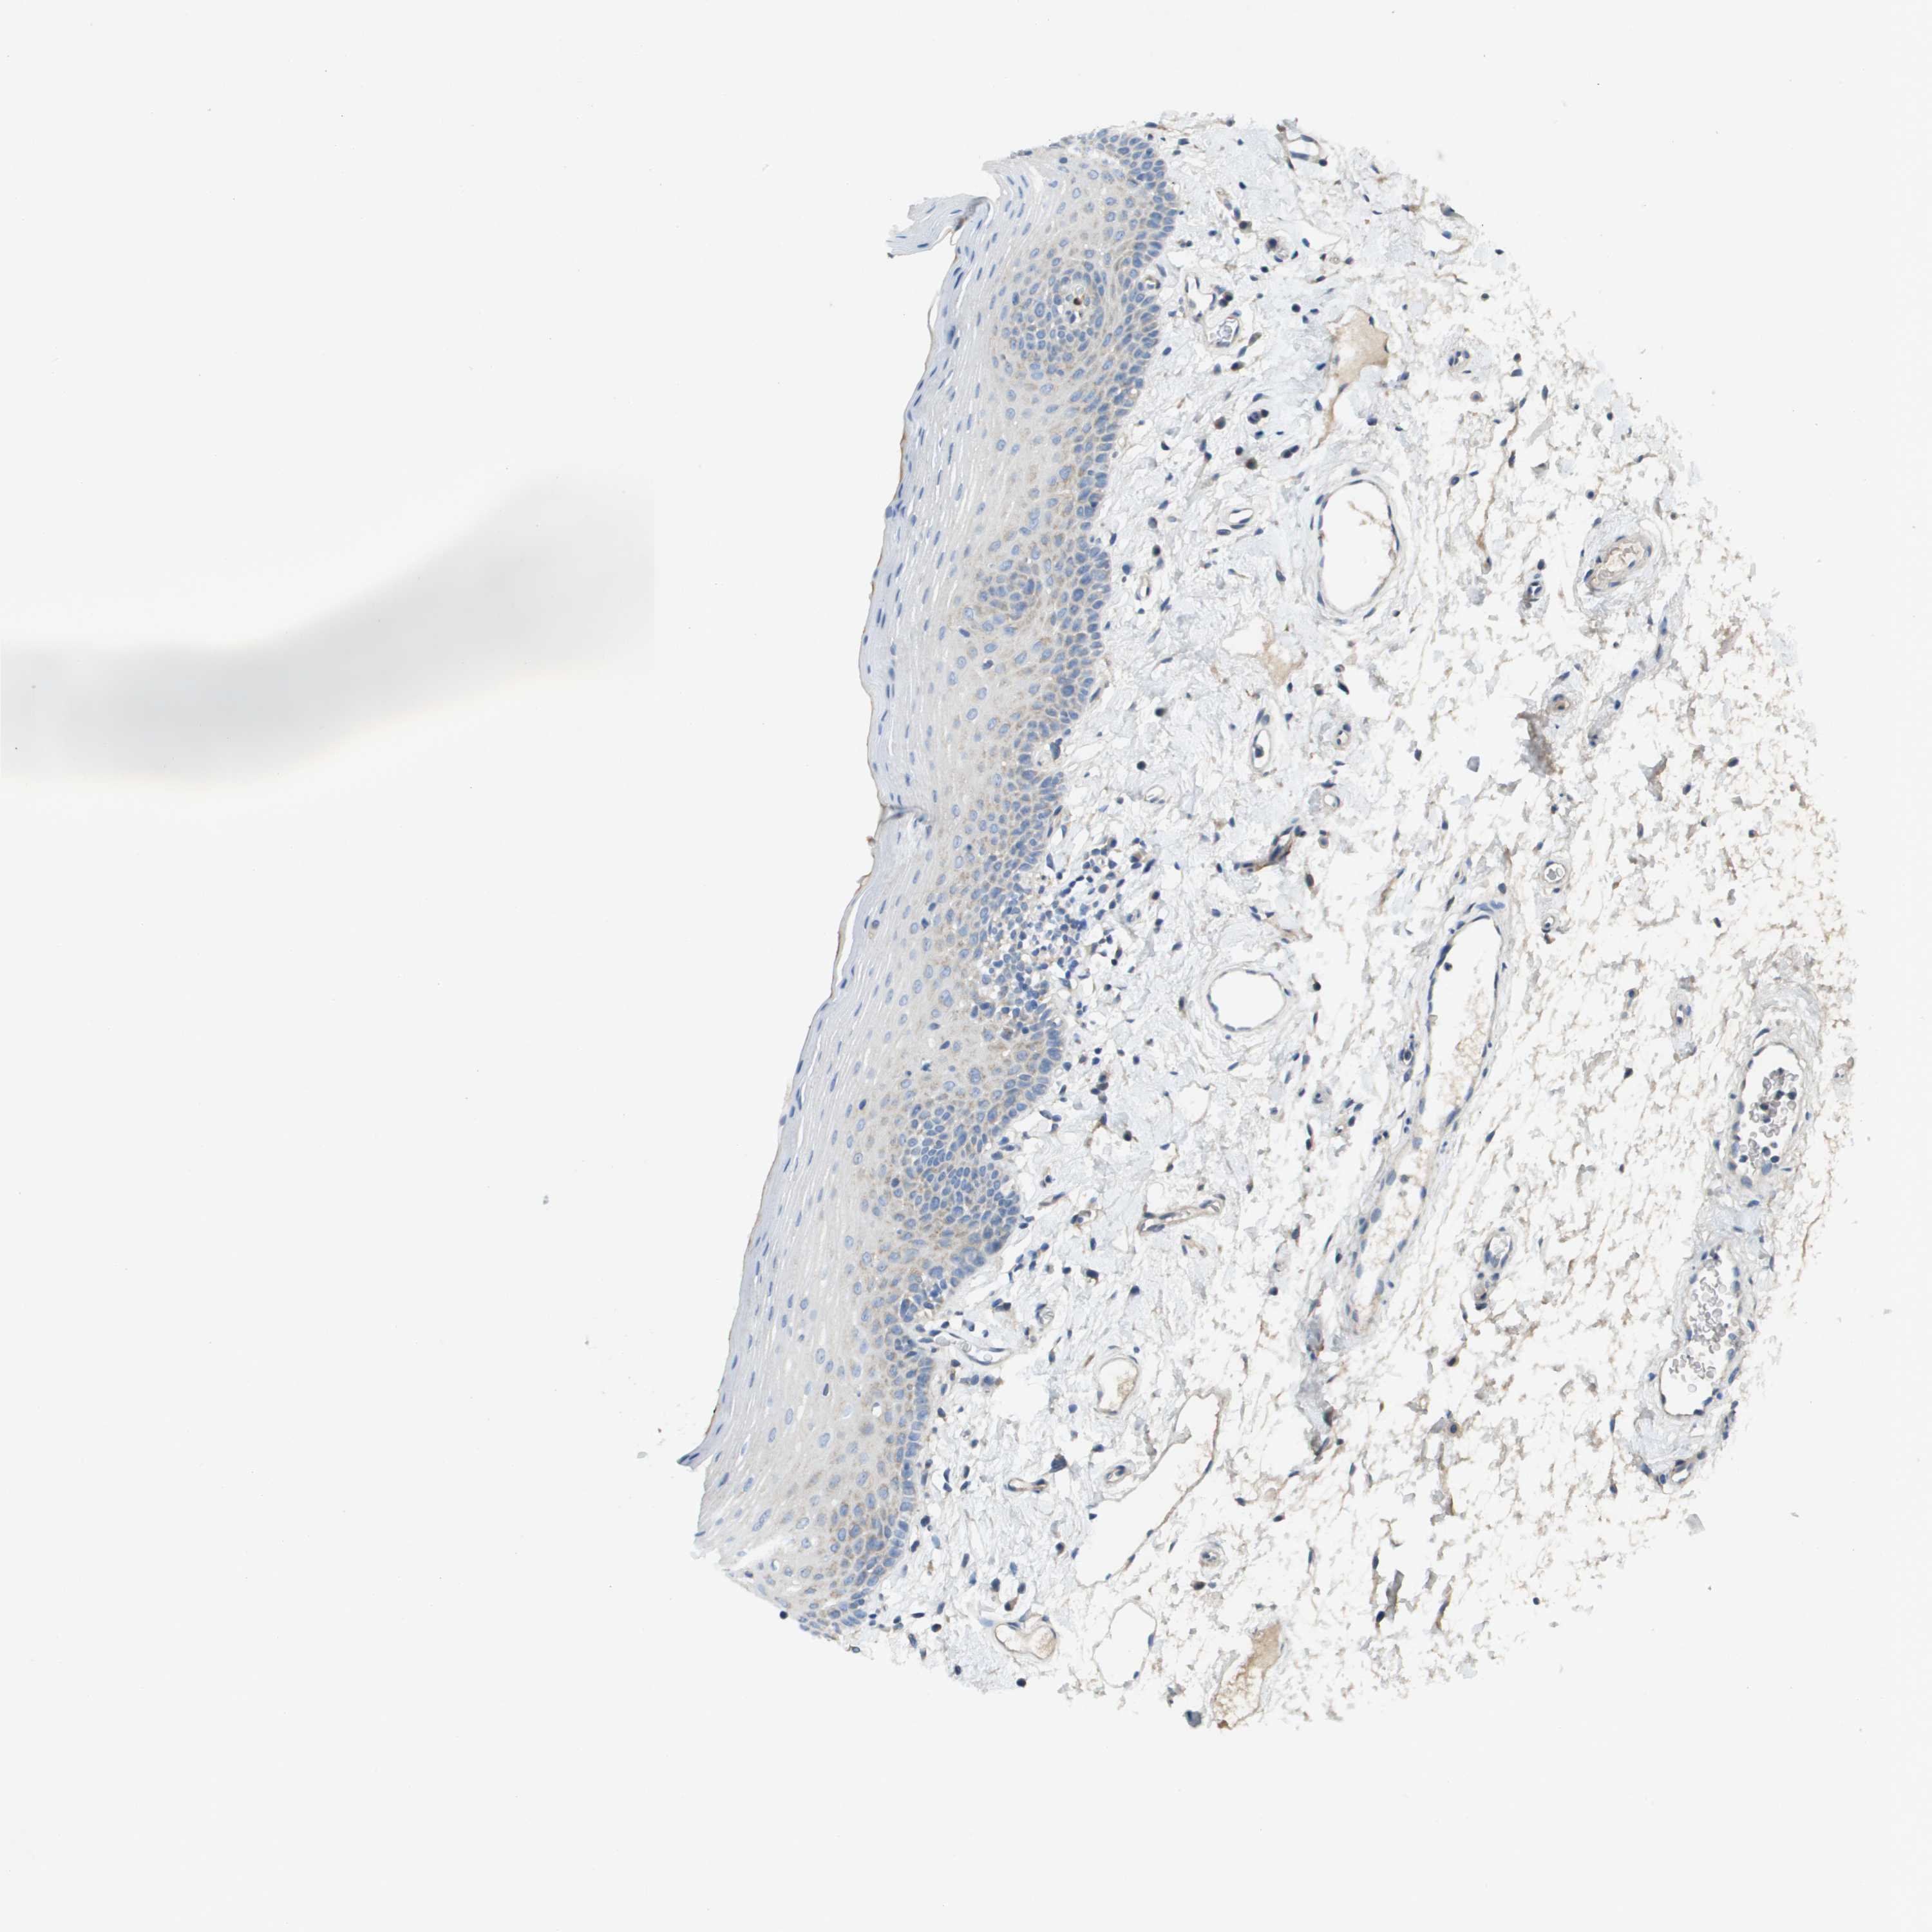

TISSUE PRIMARY DATA ORAL MUCOSA Show tissue menu

ORAL MUCOSA - Antibody stainingi

Antibody staining in the annotated cell types in the current human tissue is reported as not detected, low, medium, or high, based on conventional immunohistochemistry profiling in selected tissues. This score is based on the combination of the staining intensity and fraction of stained cells.

Each image is clickable and will lead to virtual microscopy that enables deeper exploration of all samples and also displays staining intensity scores, fraction scores and subcellular localization as well as patient and tissue information for each sample.

Antibody HPA017757

Squamous epithelial cells Not detected